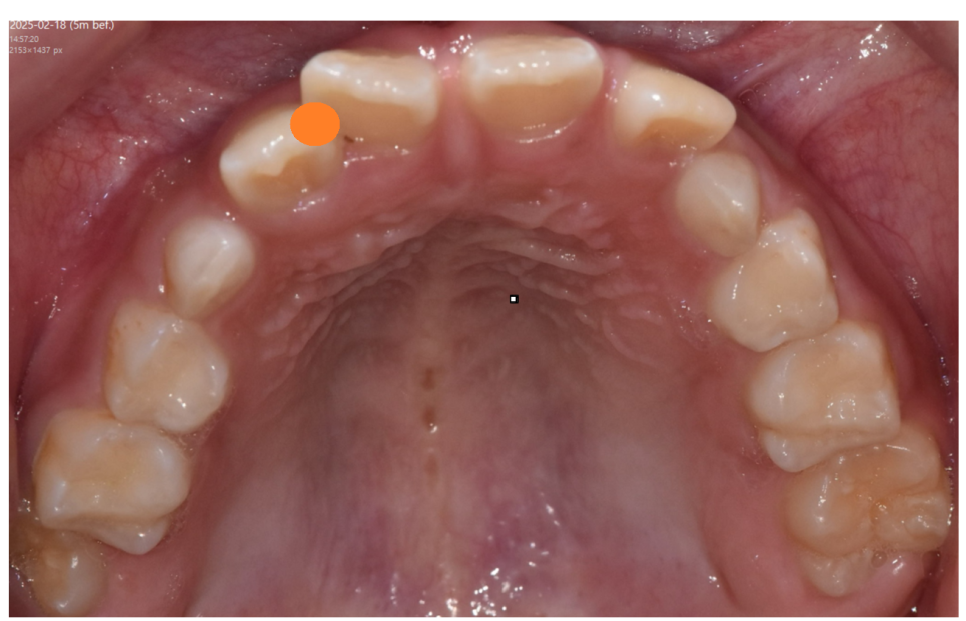

250218

덧니는 미관상 좋지 않지만

충치나 잇몸질환의 위험이 증가합니다.

칫솔질이 어려워 그렇습니다.

250218 겹쳐지는 부위는 잘 안닦이겠죠?